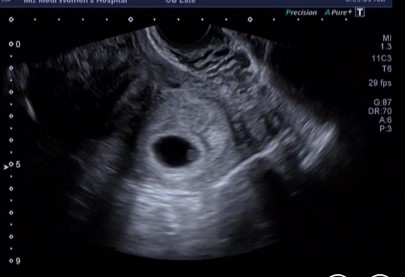

우리 아가♡ 엄마에게 와줘서 고마워 ^^

2016년 10월 14일 처음으로 아기집 확인한날 설마 했는데 정말로 와줬구나 ^^ 엄마한테 와줘서 고마워용 ♥...